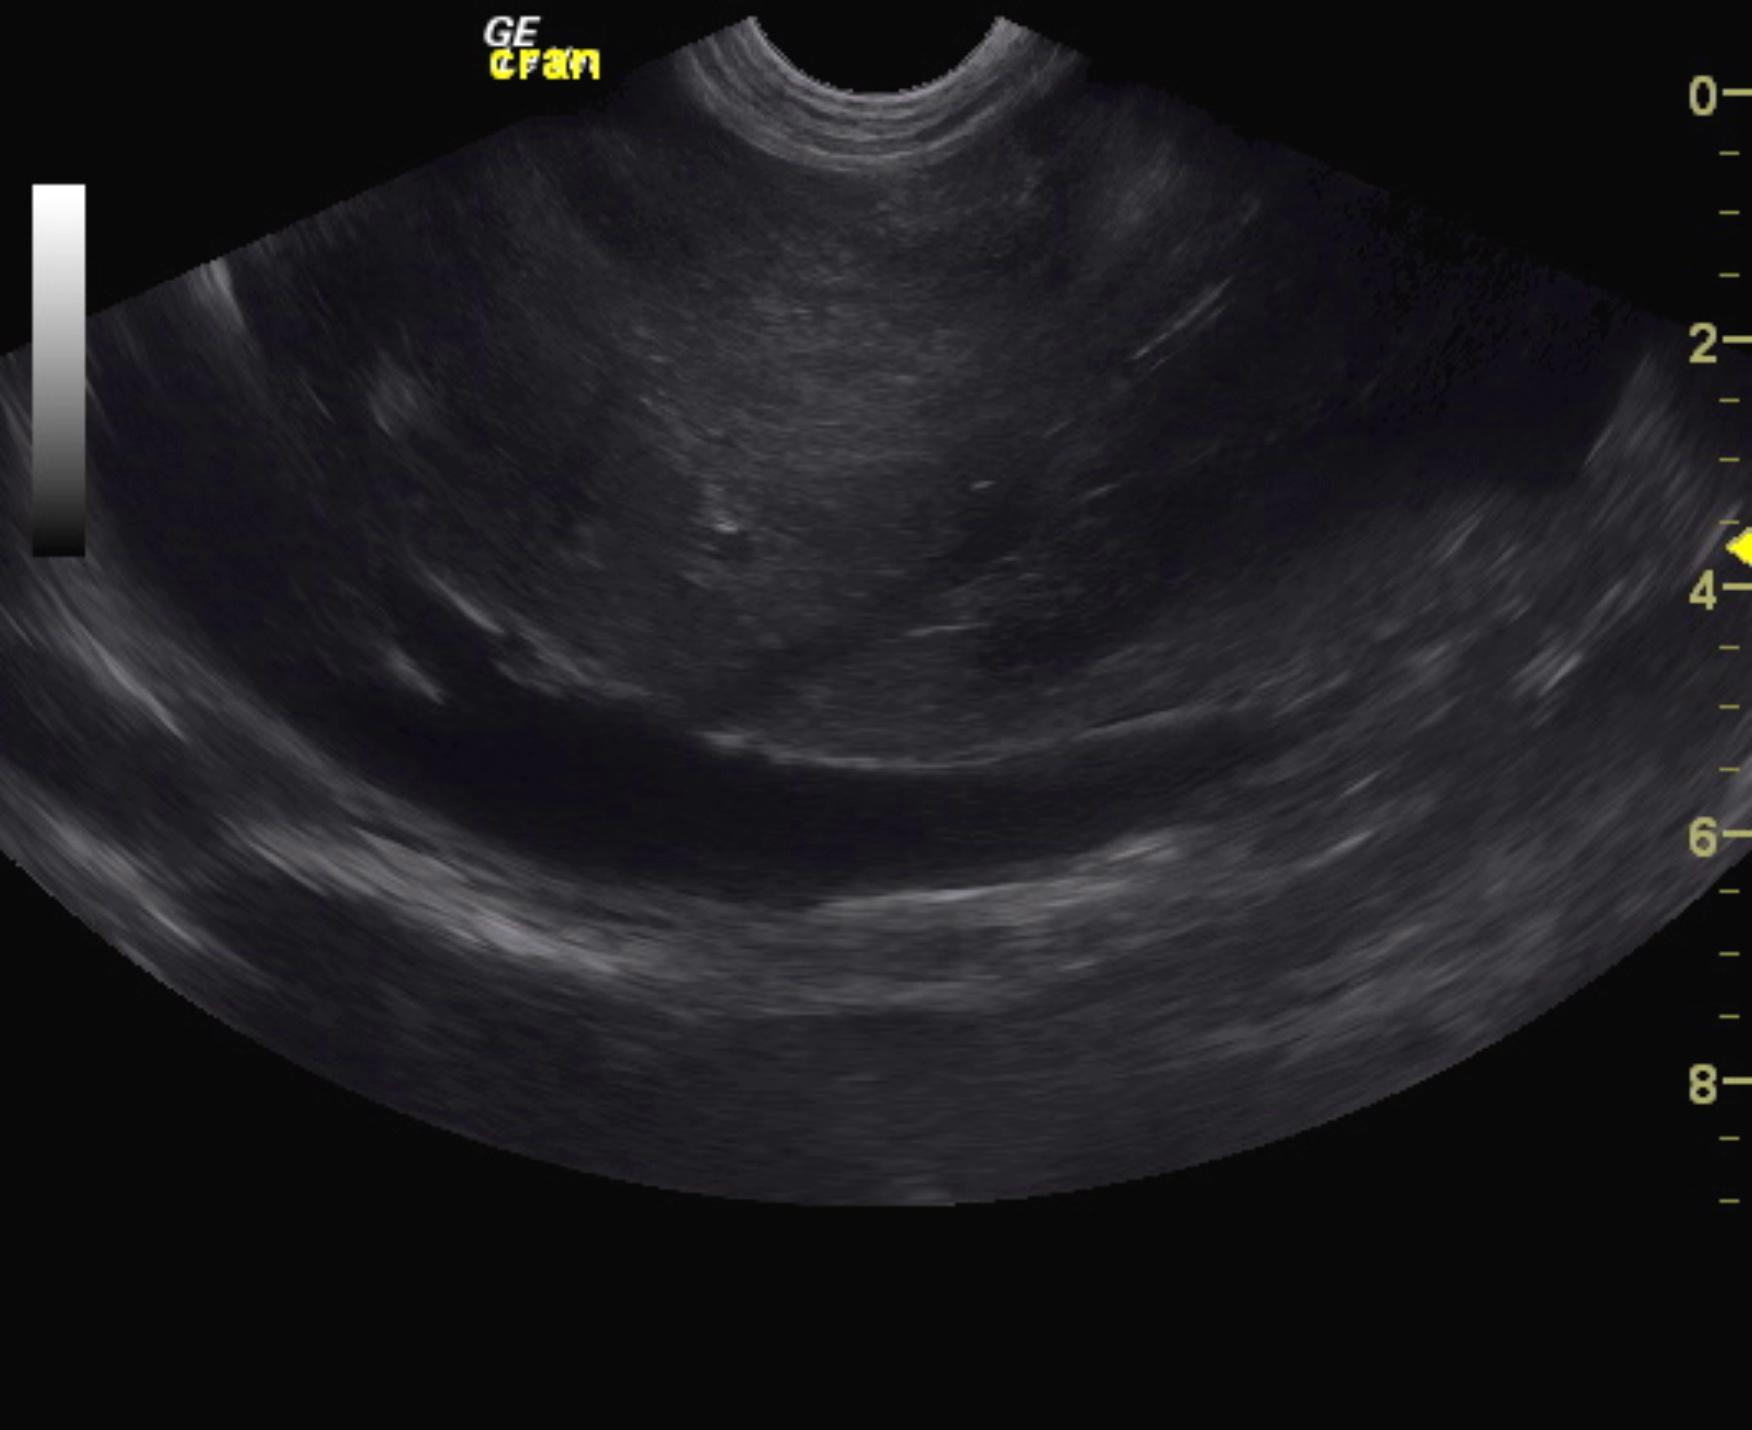

The left liver revealed a hyperechoic mass that measured 3.34 cm. This is consistent with pronounced, nodular hyperplasia or possible hepatocellular carcinoma. A separate mass that measured 4.78 x 3.4 cm with loss of detail and hyperechoic parenchyma was noted. Aside from the masses, the liver revealed swollen, irregular contour and nodular changes. Gallbladder was unremarkable. The common bile duct was unremarkable.

Heterogenous parenchymal changes were noted throughout the pancreas. This is likely owing to edema and artifact owing to the ascites. The abdomen presented a moderate amount of ascites, dilated hepatic veins and dilated vena cava.